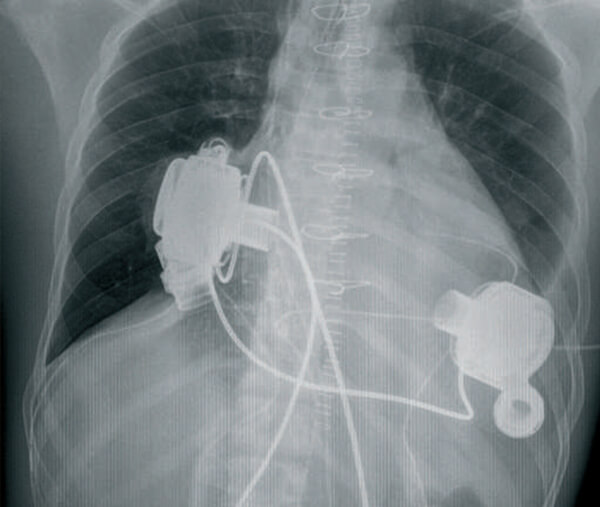

Assistance circulatoire mécanique de longue durée

Coeurs artificiels : maintenir en vie à tout prix ?